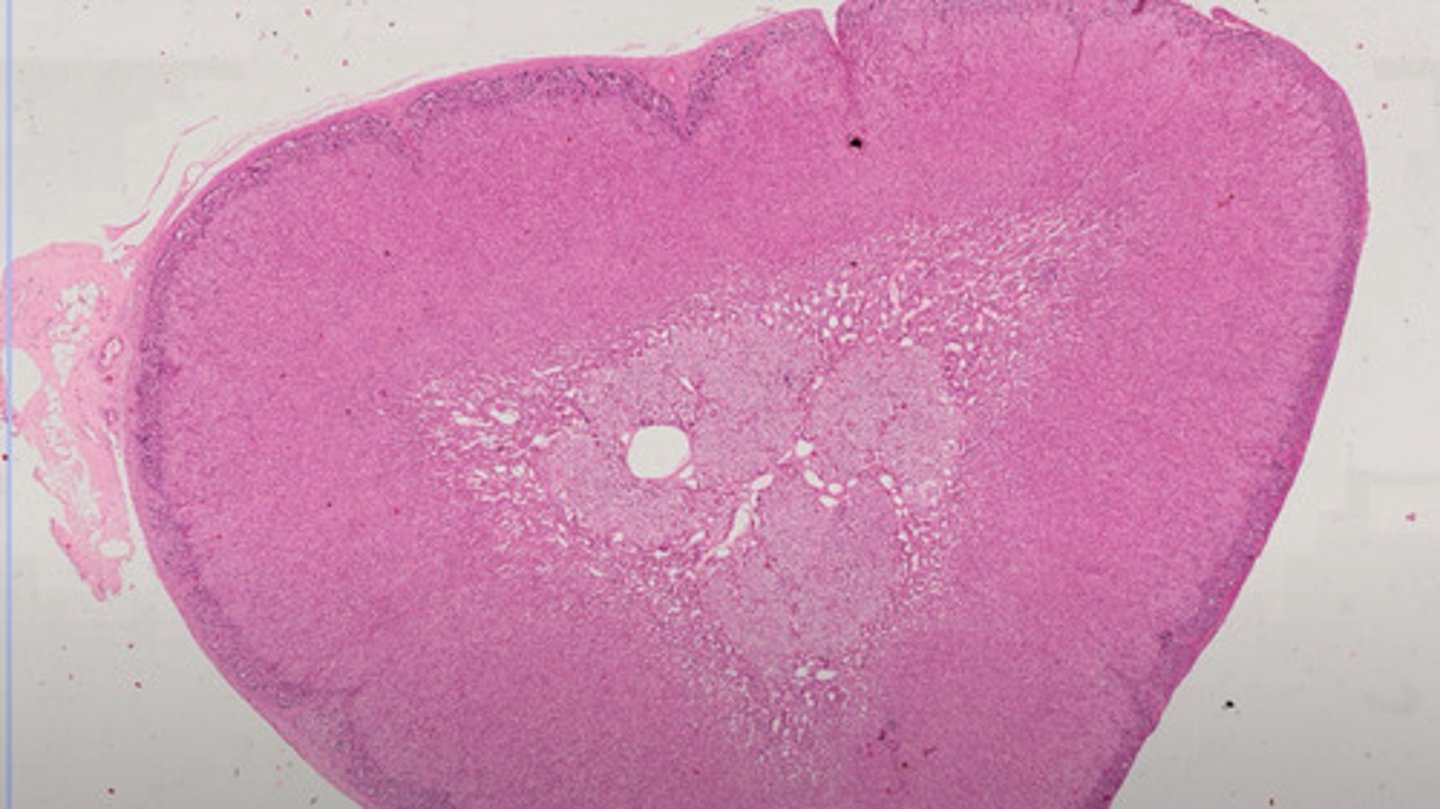

Węzeł chłonny (H+E)